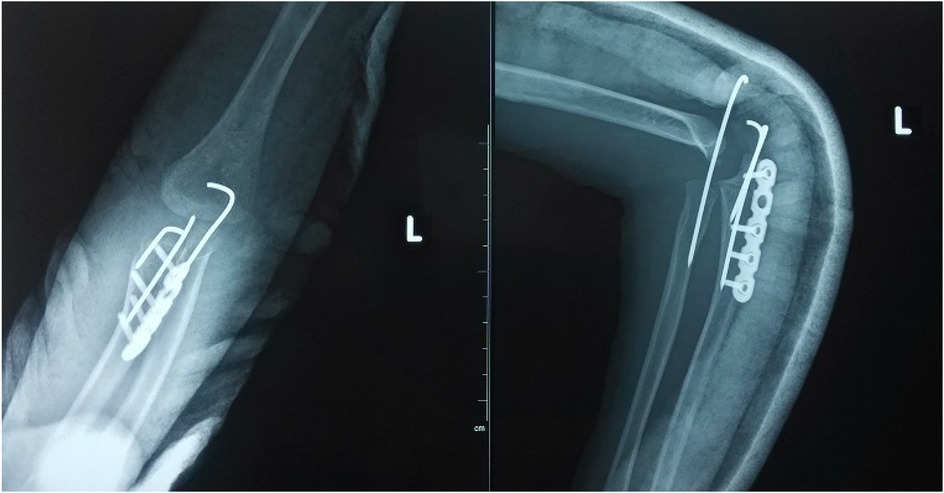

Objective: To investigate and analyze the application value of elbow arthrography in the treatment of chronic radial head dislocation in children. Methods: From January 2014 to January 2017, 15 children with chronic anterior radial head dislocation were treated (11 boys, 4 girls; average age 9 years, range 3-11 years). Intraoperative elbow arthrography was performed to assess the position of the radial head relative to the joint capsule. The nature of the dislocation was confirmed by opening the joint capsule to directly observe the relationship between the radial head and capitellum, as well as the morphology of the radial head. Reduction of the radial head was achieved via proximal ulnar osteotomy, and fixation was performed using a plate and screws with or without Kirschner wires (K-wires). Results: Elbow arthrography showed the radial head was located within the joint capsule in 12 cases and outside the capsule in 3 cases. Among the cases: All 8 congenital dislocations had the radial head within the joint capsule. Of the 7 traumatic dislocations, 4 had the radial head within the capsule and 3 outside. Direct inspection after capsulotomy confirmed the arthrography findings and revealed characteristic morphological differences. In congenital dislocations, there was no scar tissue between the radial head and capitellum, and the radial head fovea was shallow and flat. In traumatic dislocations, obvious scar tissue was present between the radial head and capitellum, and the radial head fovea was distinct. Follow-up ranged from 9 months to 4 years (average 2 years 5 months). Postoperative radiographs showed no cases of radial head re-dislocation or subluxation. Postoperative elbow range of motion improved in all patients, with no reports of pain or functional instability. Conclusion: Elbow arthrography serves as a valuable adjunct for differentiating between congenital and traumatic radial head dislocations, thereby informing both surgical strategy and the decision for supplemental fixation. When stable bony alignment is achieved, proximal ulnar osteotomy without annular ligament reconstruction represents an effective management strategy for chronic radial head dislocation in children.